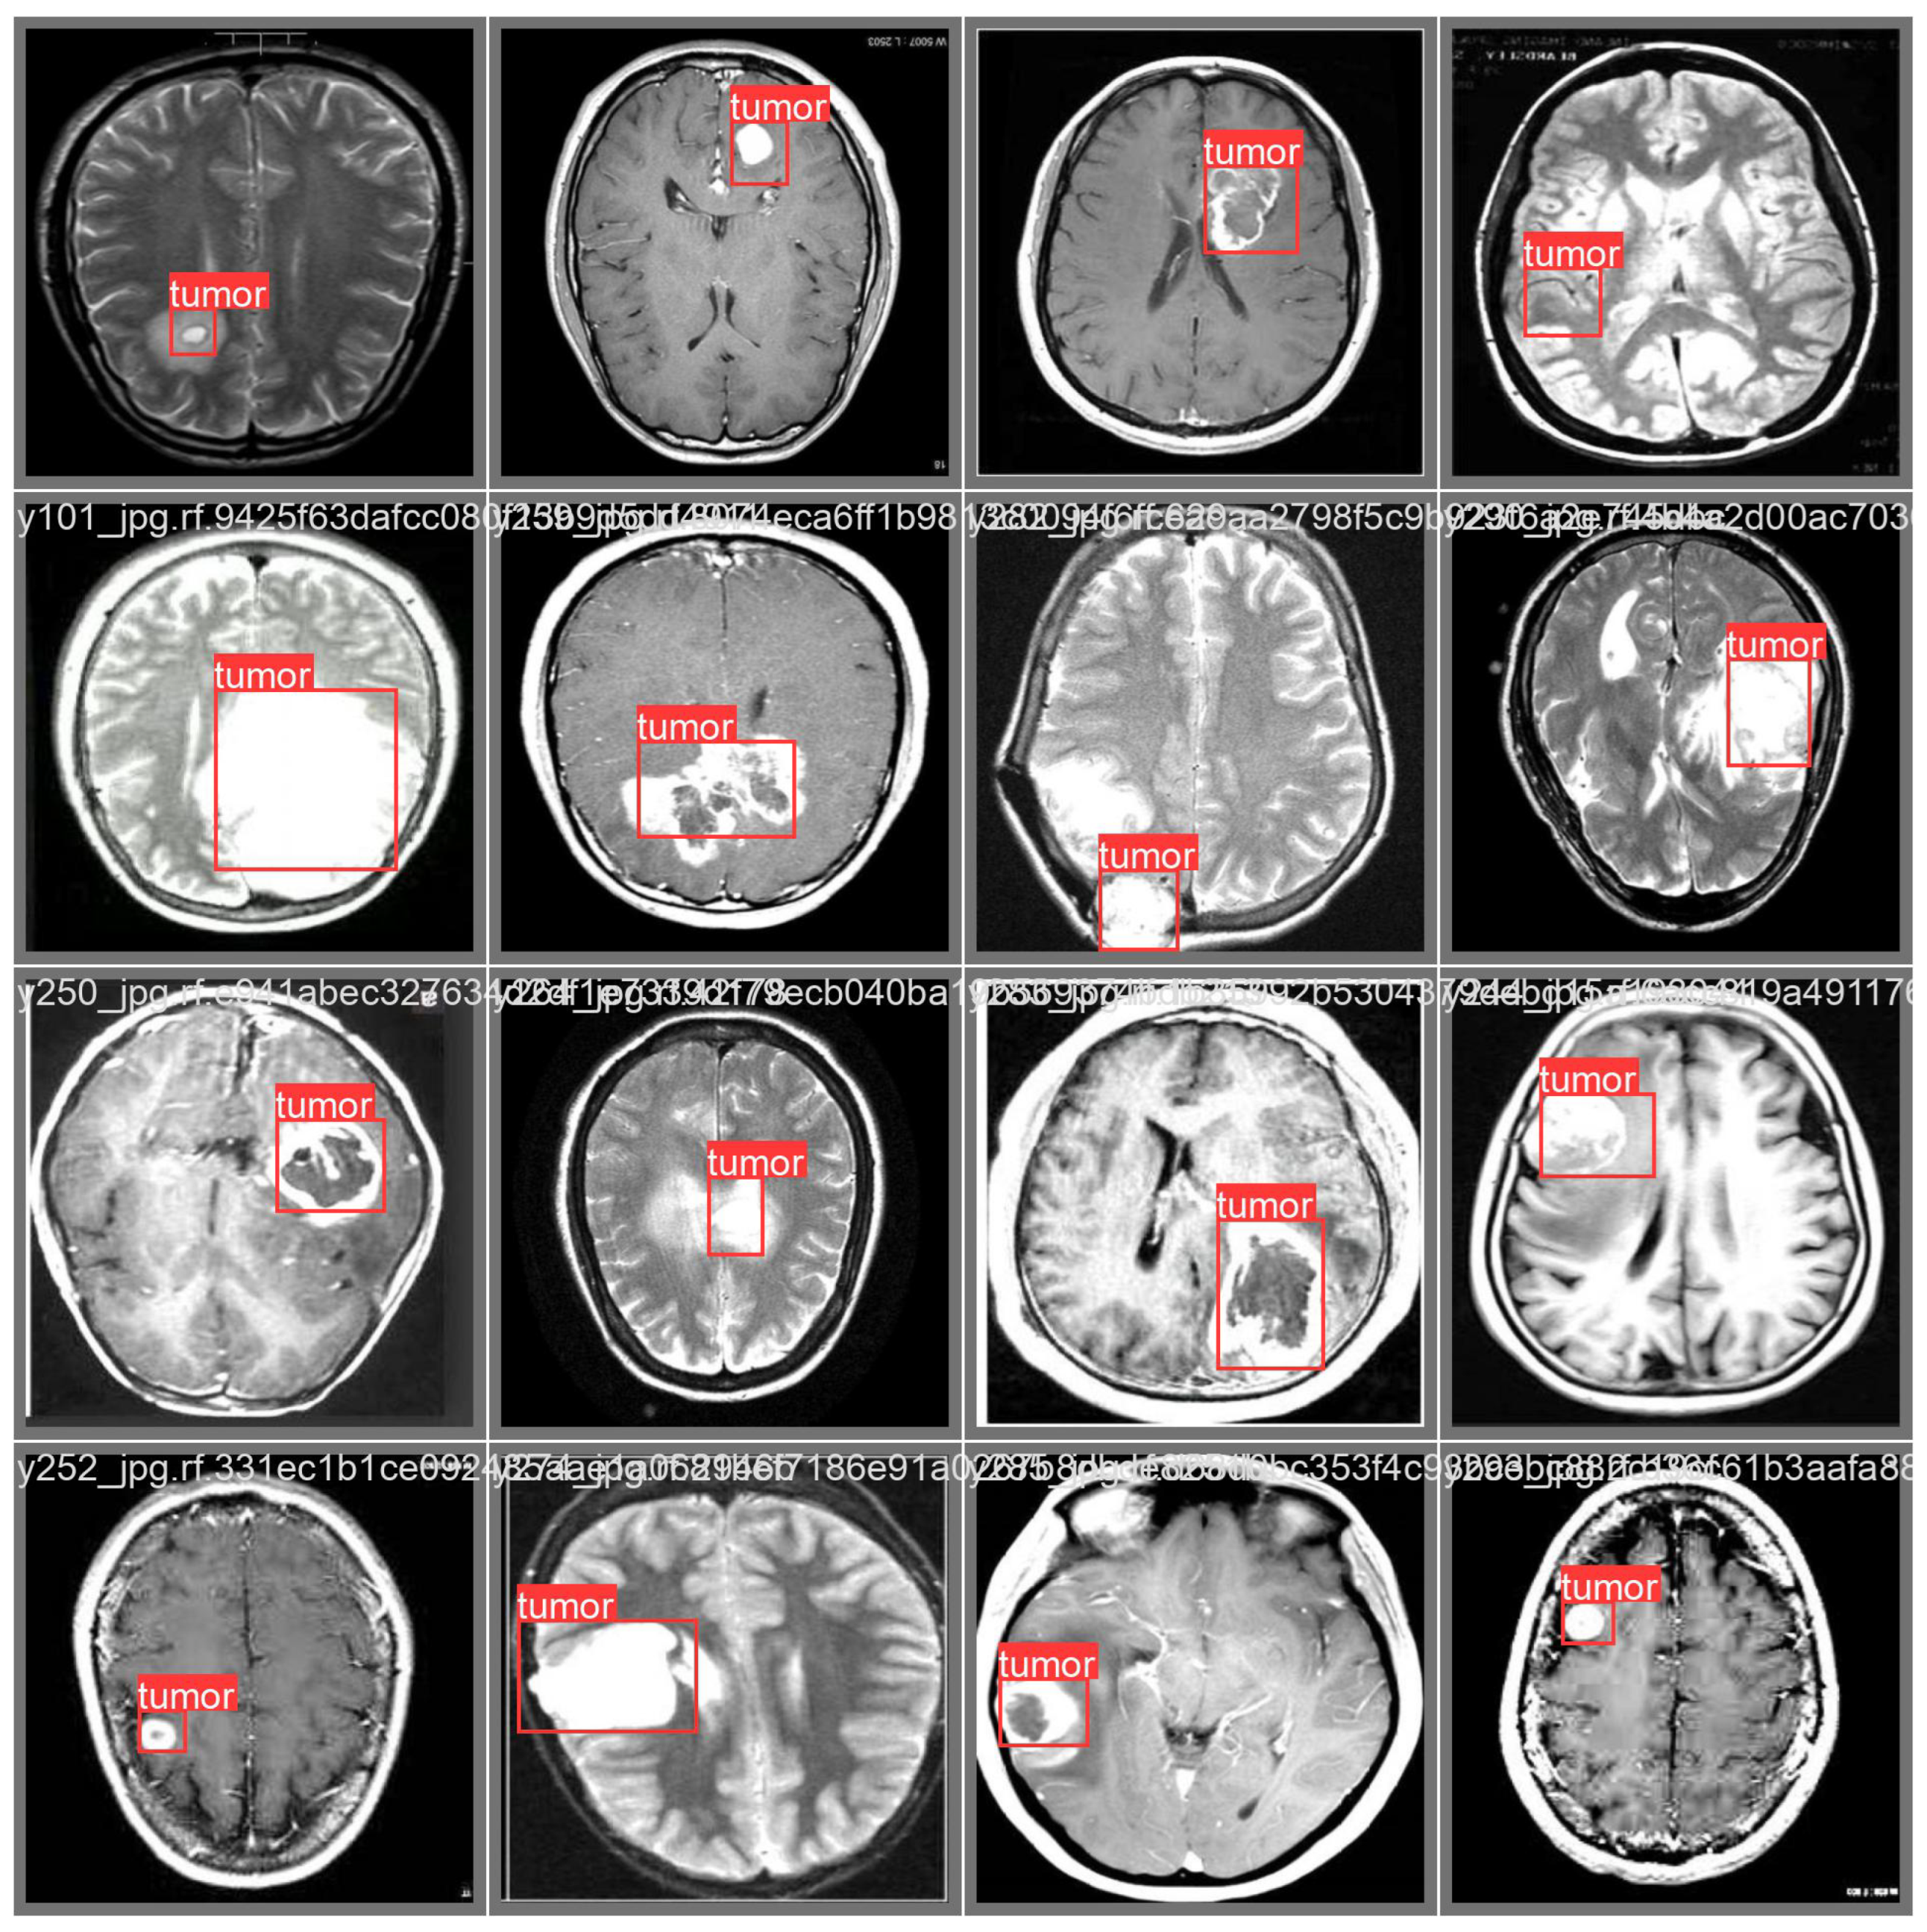

Computer Vision#

One of the most visible areas is computer vision. Models like convolutional neural networks have allowed machines to “see” and interpret images. This is the foundation of facial recognition on our phones, automated quality checks in factories, and even life-saving applications such as detecting tumors from X-ray or MRI scans. A decade ago, this level of accuracy in image recognition seemed far off, yet today it’s already part of our everyday lives.

Healthcare and Medicine#

The field of healthcare has also embraced deep learning in profound ways. Beyond medical imaging, it is being used to predict diseases, assist in drug discovery, and even recommend personalized treatment plans. These tools not only support doctors but also expand access to better healthcare worldwide.